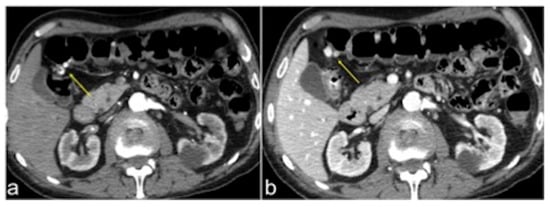

| Aorto-Enteric Fistula (Figure 31) | Bleeding in a patient with a history of surgery for aortic aneurysm. | A connection between the aorta and the intestinal lumen. Absence of adipose cleavage planes. |

| Haemobilia (Figure 32) | Melaena, haematemesis, biliary colic, jaundice, or massive bleeding in a patient with a history of blunt or iatrogenic abdominal trauma. | Presence of blood in the gallbladder and biliary tree. |